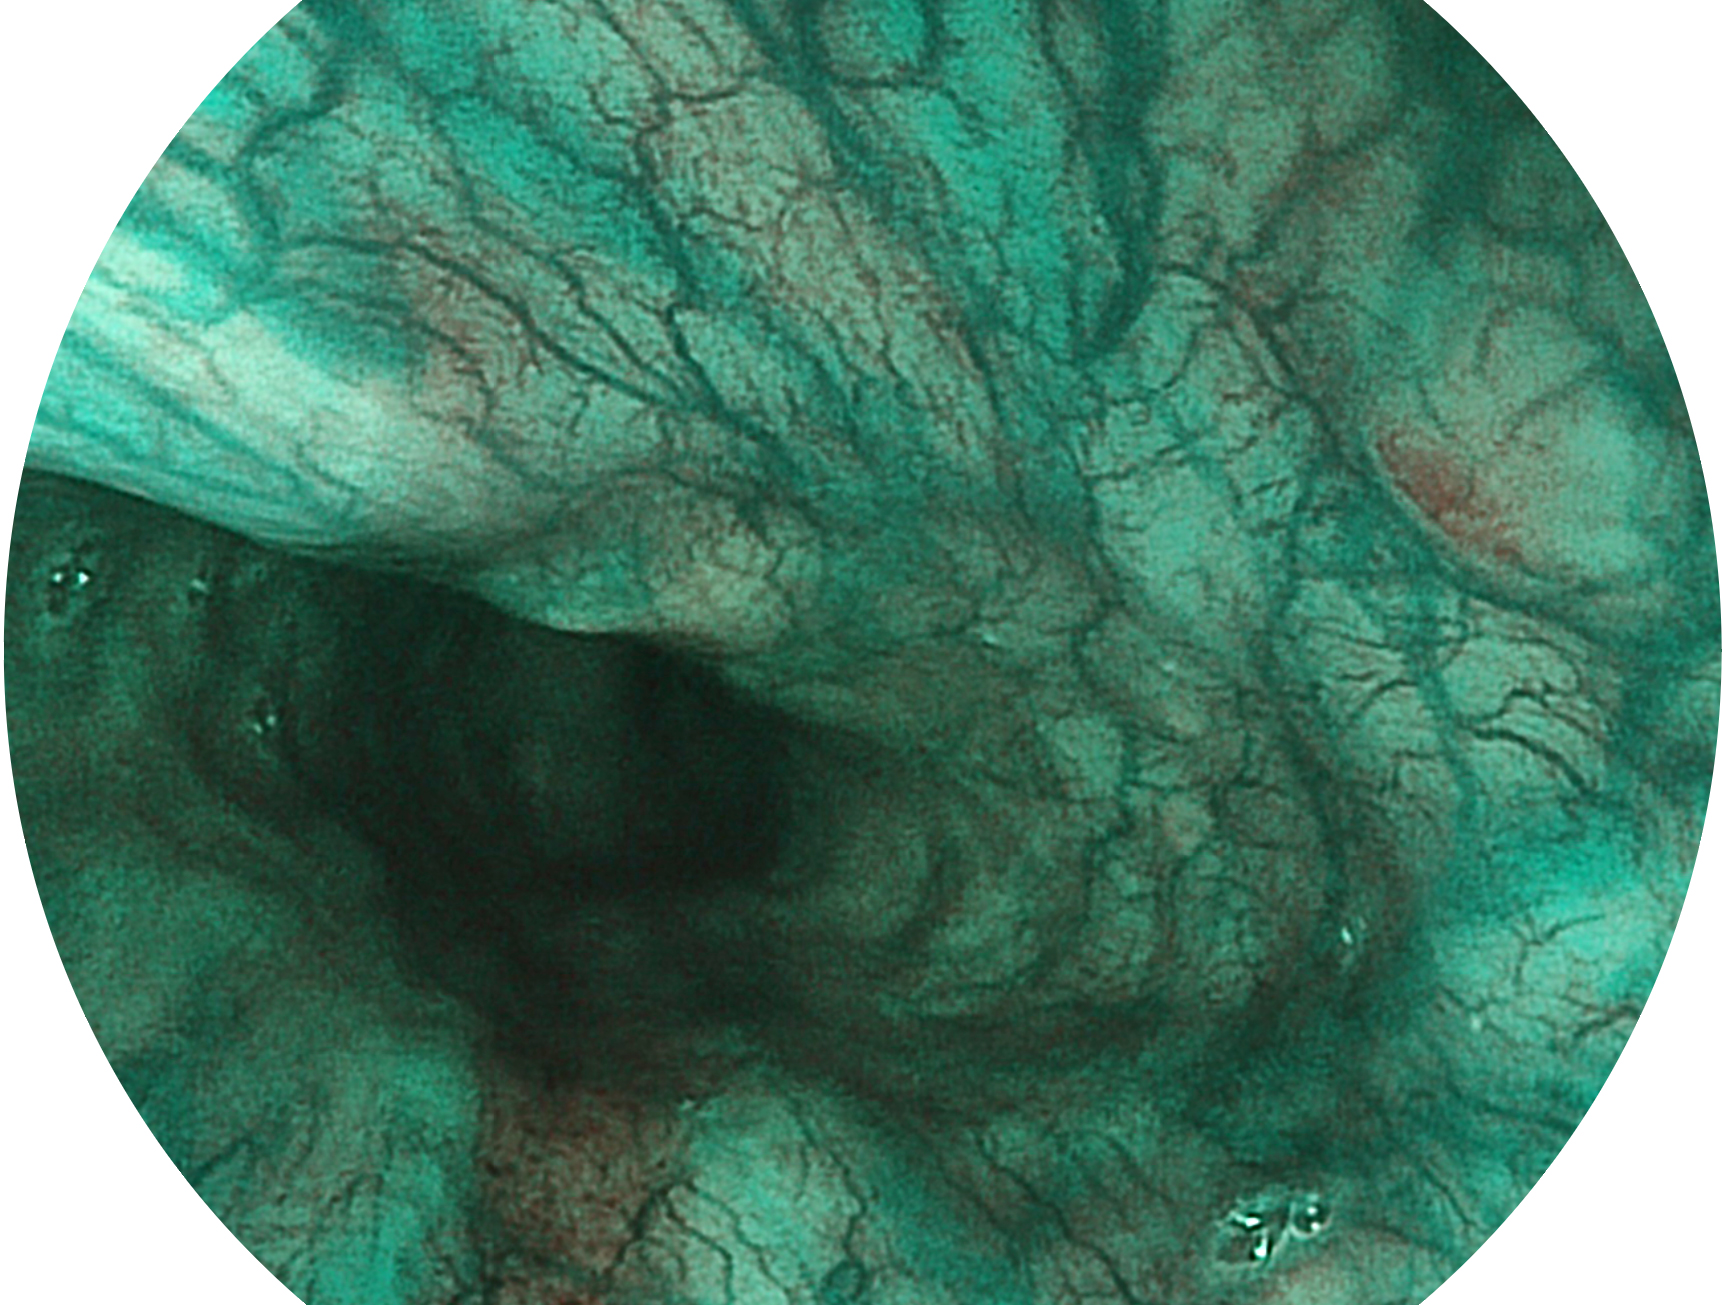

milan米兰新开发的内镜染色技术,主要是基于多波长LED 光源的开发,VLS-55Q 四波长LED 光源是由四个不同颜色的LED光按照相应照明模式所规定的特定发光比例进行合束后形成,合束后形成的照明光的光谱由红光、绿光、蓝光及蓝紫光这四个不同的波段范围构成。具有更高光谱自由度,通过光谱比例的控制,实现了聚谱成像技术,英文全称为“Spectral Focused Imaging, SFI”,缩写为“SFI”和光电复合染色成像技术,英文全称为“Versatile Intelligent Staining Technology, VIST”,缩写为“VIST”。